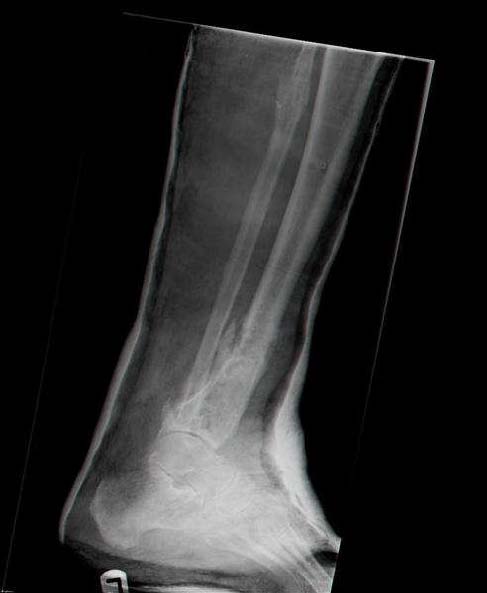

Женщина 46 лет, неудачно лечившаяся по поводу перелома голени в нижней 1\3 сначала в гипсе, поступила через 6 месяцев после остеосинтеза пластиной (рис 1). Имелась деформация в нижней 1\3 голени: варус, антекурвация, наружная ротация, два свища. Удалена пластина, дебридмент мягких тканей,

остеотомия м\б кости, аппарат Илизарова. По рентгенограммам в двух проекциях произведено планирование устранения смещений (рис 2 и 3), между вторым и третьим кольцом установлены 6 телескопических дистракторов Гесапода, данные введены в программу, и далее втечение 10 дней больная подкручивала телескопы согласно выданной компьютером инструкции. По завершению репозиции гексаподные телескопы обратно заменены на обычные штанги от аппарата Илизарова (рис 4 и 5). Еще через две недели забит гвоздь (рис 6, контроль

через 4 месяца).